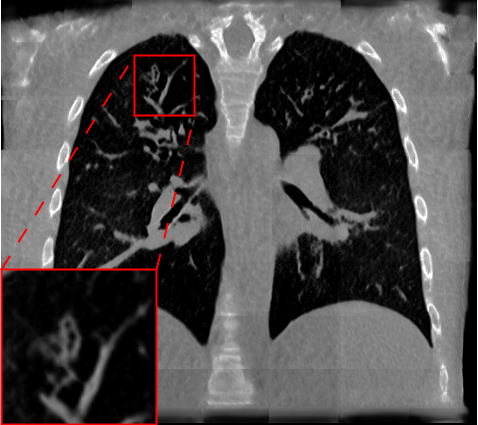

Table 3 and Fig. 5 present a comparison of the models on the reconstruction of lung anatomical regions using the TotalSegmentator (TotalSeg) pipeline with Dice score and NSD. The model trained with the AFP loss using TotalSeg’s embeddings provide the best performances. For example, when reconstructing bones, this model achieves a NSD of 0.629, outperforming the L1 loss model (NSD: 0.493) as well as perceptual loss (NSD: 0.499). A combination of AFP loss using NaviAirway and HAL’s embeddings also delivers positive results, whereas other models exhibit notably poorer reconstructions especially in the bones.

| Loss | Muscle/Organs | Bones | ||

| Dice | NSD | Dice | NSD | |

| L1 | ||||

| Perceptual | ||||

| AFP TotalSeg | ||||

| AFP Navi | ||||

| AFP HAL | ||||

| AFP Navi + HAL | ||||

Note: *Indicates statistical significance compared to L1 loss, as measured using the Wilcoxon signed-rank test. P values less than 0.05 were considered statistically significant.

|